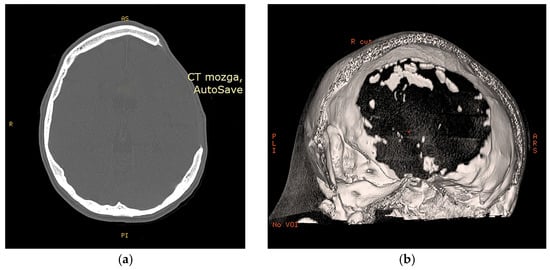

3.2. Radioogical Findings